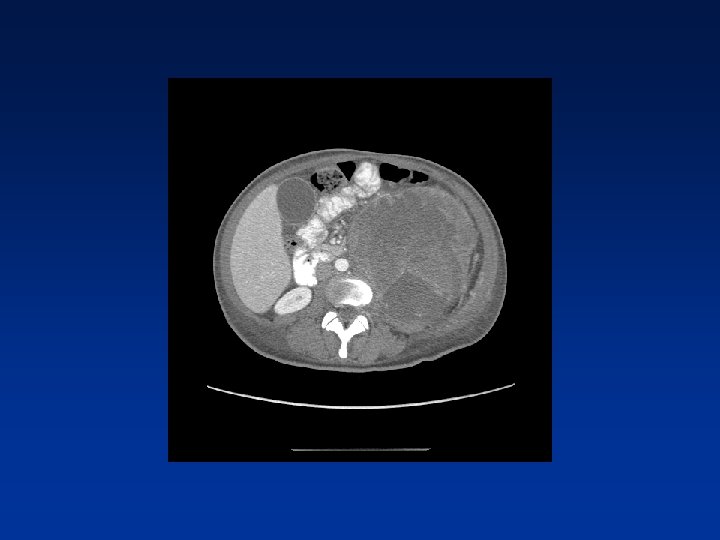

CASE